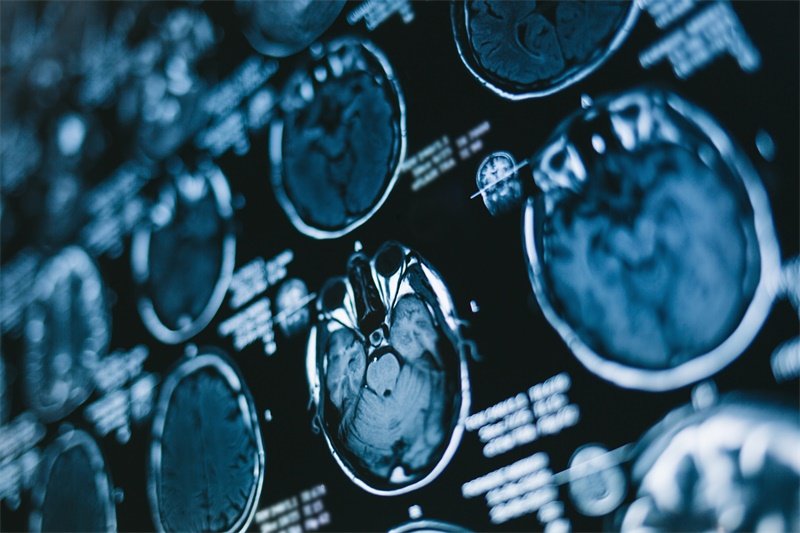

核磁共振成像(MRI)

MRI 是一种非侵入性的影像学检查方法,可以详细观察到脑部结构,尤其是下丘脑区域的改变。MRI可以帮助医生评估肿瘤的大小、形状和对邻近结构的影响。

计算机断层扫描(CT)

CT扫描 也可用于评估下丘脑的病变。虽然它的分辨率不如MRI,但在急诊情况下,它可以快速提供有关脑部情况的初步信息。

患者应遵循医生的建议,定期进行 MRI或CT检查,以监测是否有复发的迹象。这可以帮助早期发现问题,并及时进行干预。